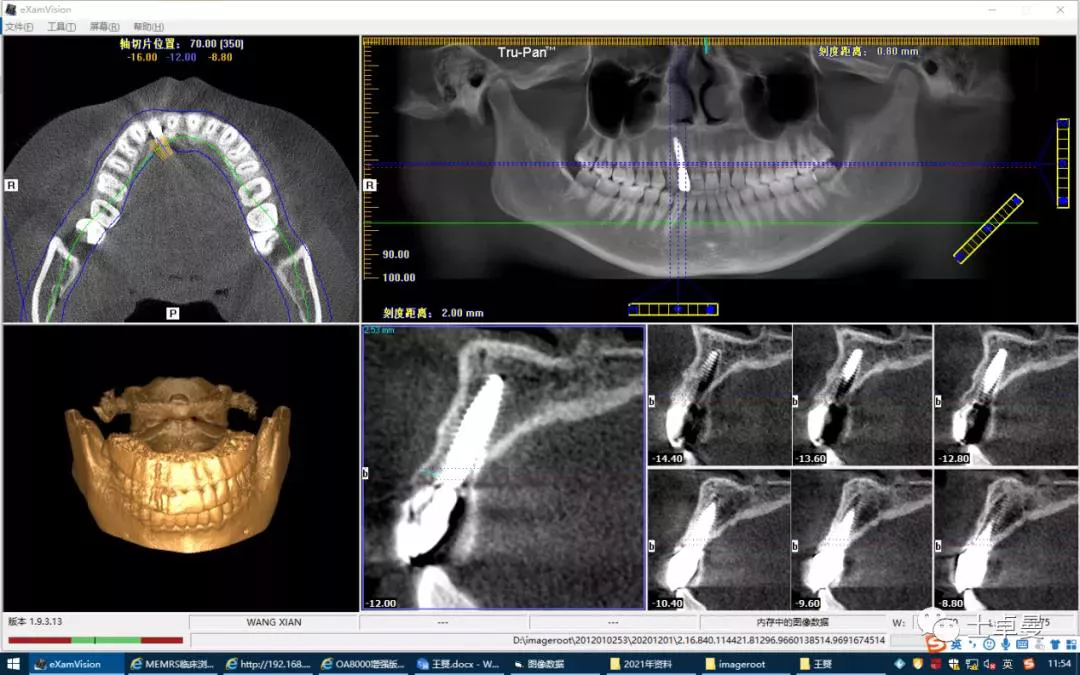

·        CBCT 检查

·       12 断根,根尖区剩余骨高度充足,可用骨高度19mm,骨宽度7.2mm。

术前 CBCT

·        CBCT显示种植体三维位置良好;

术后 CBCT 显示种植体三维位置良好

术后三年的CBCT

不同时期CBCT截图